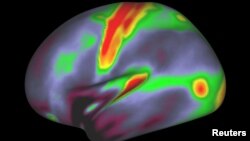

Neuroscientists acting as cartographers of the human mind have devised the most comprehensive map ever made of the cerebral cortex, the part of the brain responsible for higher cognitive functions such as abstract thought, language and memory.

Using MRI images from the brains of 210 people, the researchers said on Wednesday they were able to pinpoint 180 distinct areas in the cerebral cortex, the brain's thin, wrinkly outermost layer made of so-called gray matter.

The regions were mapped based on features such as cortical thickness and the amount of insulation, called myelin, around nerve-cell connections.

The researchers also used MRI data on cortical activity when people carry out tasks such as listening to stories, computing math problems and looking at other people making various facial expressions.